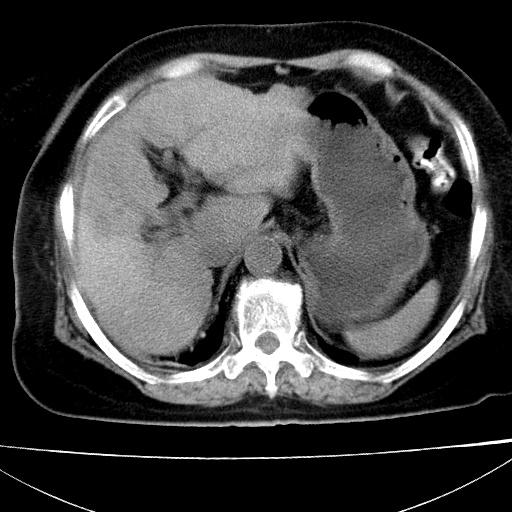

患者女74岁;右上腹胀痛1月,伴恶心,无发热;生活在疫水区。有术后病理及术后半年的追踪ct.

1)慢性血吸虫病(典型)。2)肝硬化。3)肝癌?4)胆囊炎。5)少量腹水。6)右侧少量胸腔积液。

支持.边缘见高密度线条样钙化影.

肝脏体积缩小,肝裂增宽,边缘不平呈波浪状,肝右叶见分隔状条索形钙化,亦见多结节低密度灶,边界不清,肝周可见少许液性暗区,胆囊增大内密度均匀,脾脏下缘低于脏脏的下缘,胸腔亦见液性暗区,余未见明显异常.

诊断:1肝硬化并慢性吸血虫病,脾肿大

2肝内占位,考虑肝癌可能性大,建议做增强

3胆囊炎, 4少量腹水及胸水